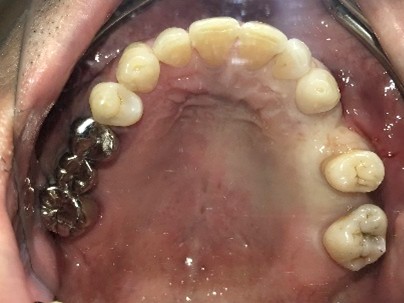

男性Kさん 50代(インプラント)

歯がグラグラするところ、むし歯のところ、しみるところ、被せ物がとれたところ、歯茎が腫れて血が出るところ、歯が抜けているところがある。すべて治したい。

治療内容

残っている歯を抜歯し、上下インプラント治療をしました。

所感

歯周病が進行している歯、むし歯が進行している歯がほとんどで、レントゲンを撮り、詳しく診てみると、ほとんどの歯を保存することができないことがわかりました。抜歯後は、入れ歯かインプラントの方法があります。治療開始前に患者さんに詳しく現状を説明し、治療法についてじっくり相談しました。自分の歯と同じような感覚で食事できるインプラント治療を選択されました。治療後、表情がとても明るくなり、口元がとても自然で10歳以上若返ったように感じました。「時間はかかりましたが、インプラントにして本当に良かったです!」と素晴らしい笑顔でお話ししてくださいました。

上顎:¥3,280,000(税込)

下顎:¥3,280,000(税込)